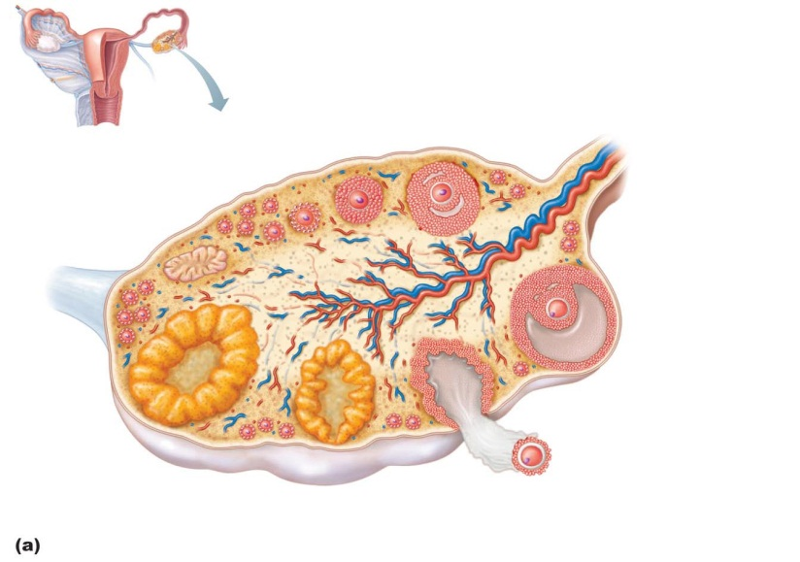

Female reproductive system

infundibulum

round ligament

cervix

vagina

uterosacral ligament

uterine tube

within the ovary after ovulation, progesterone is produced by the

corpus luteum

diploid stem cells of the ovaries

oogonium

The double layered membrane around the uterus is

perimetrium

name the dominant follicle which is selected for ovulation

secondary oocyte

progesterone level in a normal uterine cycle

the ovary

primary follicle

theca folliculi

primary oocyte

zona pellucida

antrum

secondary oocyte

corpus luteum